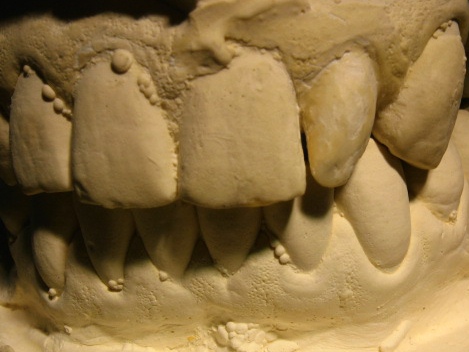

Las anomalías dentales son un grupo de alteraciones morfológicas, que se pueden expresar en la corona o en la raíz dental; aparecen durante el desarrollo de los órganos dentales, se ha establecido que tienen un componente genético y molecular importante. También se han planteado influencias medioambientales, traumáticas y microbiológicas. Las anomalías morfológicas dentarias son comunes, y se presentan con una incidencia de 74,7% según Freer (1998). Los dientes cónicos, en clavija o reducidos tienen una incidencia menor y muestran mayor incidencia en dentición permanente, así como en los incisivos laterales superiores. El mencionado defecto va a ser origen de alteraciones en la oclusión, la longitud de arco, compromisos estéticos que van a afectar la autoestima del paciente. El propósito de este trabajo es presentar dos casos de dientes cónicos, uno en dentición permanente, otro en dentición temporal relacionándolos con el marco teórico encontrado en la literatura sobre las influencias genéticas que juegan un papel importante en la aparición de la mencionada anomalía, aunque no se pudo realizar el estudio genético que se quisiera a causa limitaciones económicas.